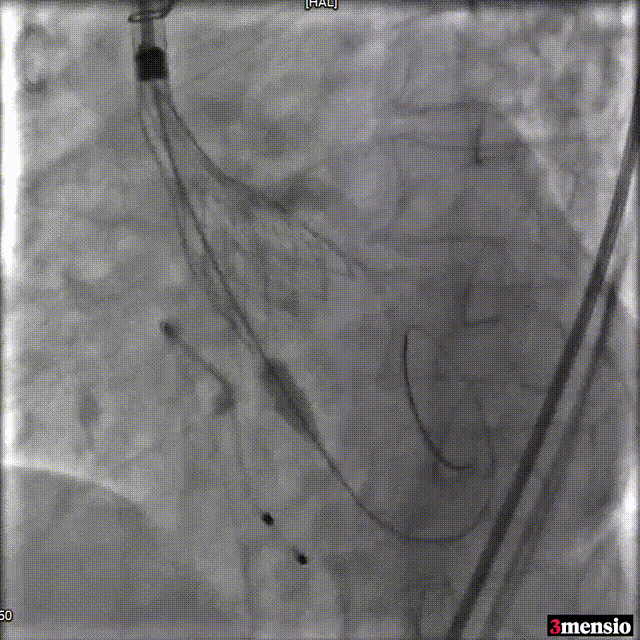

2.双超硬导丝及Snare辅助过弓,避免损伤升主动脉。

手术过程概览:

Snare辅助输送系统过弓